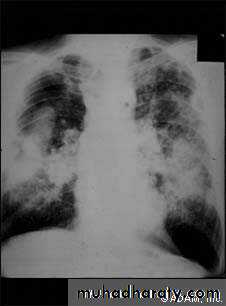

Pulmonary fibrosis caused by prolonged inhalation of coal dust. Which divided into;1-Simple coal worker's pneumoconiosis (SCWP); scattered discrete fibrotic lesions, does not cause pulmonary function abnormalities or progress following cessation of exposure.

2-Complicated pneumoconiosis; large dense masses appear mainly in the upper lobes (also known as progressive massive fibrosis, PMF). Presented as cough, production of sputum, that may be black (melanoptysis) and breathlessness. Respiratory failure after cessation of exposure and right ventricular failure.

The clinical and radiological features are similar to those of coal worker's pneumoconiosis, with multiple well circumscribed 3–5-mm nodular opacities, predominantly in the mid- and upper zones